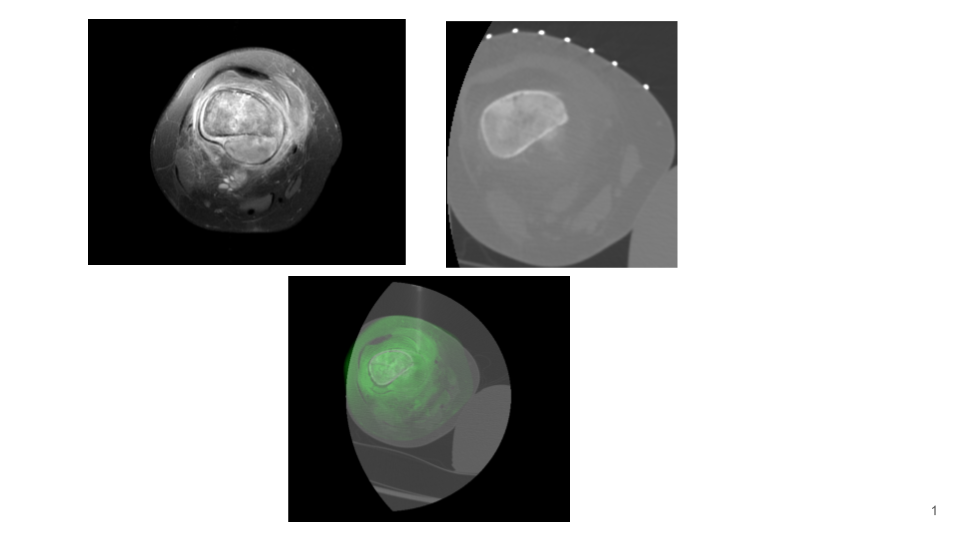

IGTFusion used to guide and confirm accurate biopsy needle placement in soft tissue mass adjacent to femoral bone tumor that was not visible on CT during the procedure, but was visible on the pre-treatment MRI.

- Registered a pre-procedure MRI with procedural CT

- Fusion adjusts for rotation of femur between images due to leg positioning

- Saved procedure time by identifying the occult soft tissue mass for biopsy